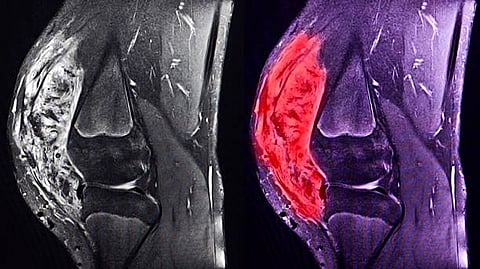

Sarcomas are cancer tumours found in e.g. the bones, muscles or fatty tissue. It is a rare type of cancer seen in only one per cent of cancer patients. It is complex and difficult to treat.

Sarcomas are cancer tumours found in i.a. the bones, muscles or fatty tissue. There are two main types: bone sarcoma and soft tissue sarcoma (muscles, fatty tissue, connective tissue, blood vessels and neurilemma).